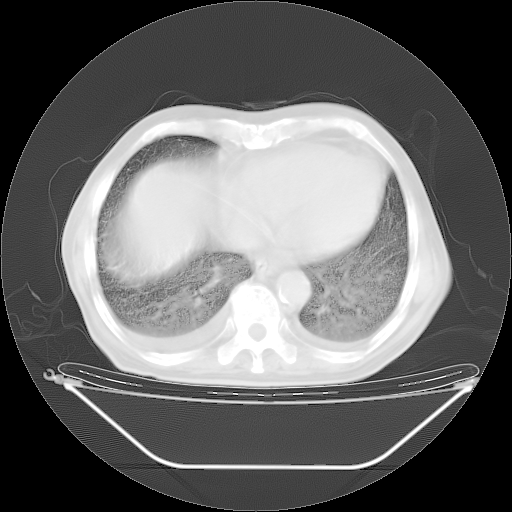

今天复查肺部CT,发现双肺广泛磨玻璃样改变。所以我把3月19日和5月9日相隔50天的肺部CT上传。请大家会诊。

5月9日肺部CT(在4月27日齐鲁医院肺部CT描述部分肺组织磨玻璃样改变,12天后肺组织广泛磨玻璃样改变)

2009年5月9日肺部CT

大致读了系列胸部CT:纵隔窗无明显异常,肺窗:从4、27至今:主要是双肺中下野外带可见毛玻璃样改变,目前处于急性肺泡炎阶段,至于原因考虑1、结替组织或胶原血管性疾病所致?2、恶性疾病如恶组在肺部所致的表现或细支气管肺泡癌?3、药物或其它原因如肺蛋白沉着症所致肺泡炎目前不太可能?总之,明天就去请我院的呼吸科、感染科、血液科和临免专家会诊哈。